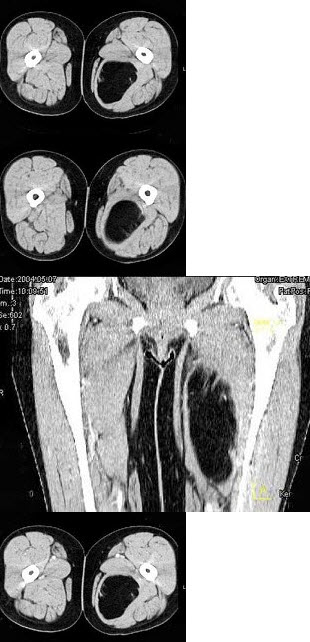

女,52岁,左小腿肿胀两年余,活动后稍加重,不痛不热,结合所提供的图像,最可能的诊断是()A: 大腿错构瘤B: 大腿畸胎瘤C: 大腿平滑肌瘤D: 大腿囊肿E: 大腿脂肪瘤

女,52岁,左小腿肿胀两年余,活动后稍加重,不痛不热,结合所提供的图像,最可能的诊断是()

- A: 大腿错构瘤

- B: 大腿畸胎瘤

- C: 大腿平滑肌瘤

- D: 大腿囊肿

- E: 大腿脂肪瘤